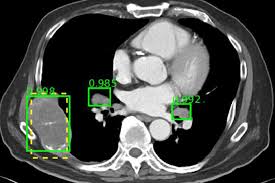

X: X-Ray Department

I believe the X-Ray/Radiology Department was in the basement of the National Institutes of Health Clinical Center where I was working but I’m not sure because I don’t remember going there on my own but usually following an entourage of white coats including the physician who was the head honcho studying a rare disease a couple of residents and a student or two and me the nurse practitioner taking up the rear happy to be part of this group and because I get to hear what the radiologist has to say when he points out the very subtle findings in the MRI or CAT scan or whatever x-ray the patient has had hoping

to identify if the disease being studied was causing the symptom that the patient was having so much so that he and his family came all this way from whatever state to get a diagnosis and they are upstairs in the waiting room on pins and needles hoping for clarification but I have been around this Institute long enough to know that most times there is no definitive answer and when the patient and his family hear that the diagnosis is inconclusive and look downhearted the primary investigator says that sometimes no diagnosis is better than a horrible one with no cure but that doesn’t make the patient or family feel better and I am sad for them because I know how much they wished to hear that their ailment had a name and a cure and they are disappointed to have traveled all the way to the NIH to get no answers however I still feel honored to be part of this research project although the part I play is rote but necessary in moving the research study along even if I don’t have a PhD in a research specialty nor am I one of the leading investigators in this important study I hope my nursing contribution has been helpful and I find out after I have given my notice and leave to follow my husband to another state because he has a new job that my position was filled by two nurse practitioners.